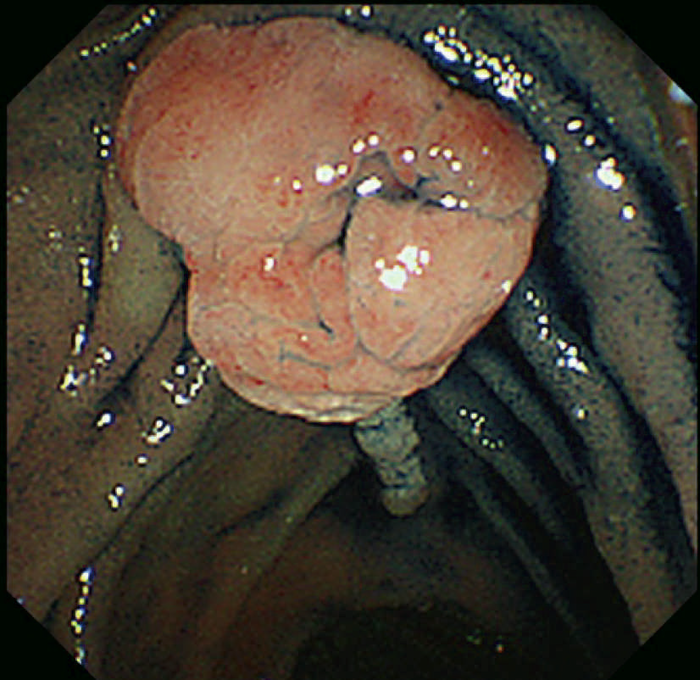

- 古典型FAPは数百から数千の大腸腺腫性ポリープを特徴とし,平均16歳(範囲7~36歳)から発症し始める。古典型FAPの場合,95%が35歳までにポリープを形成し,大腸切除などの介入を行わなければCRCは避けられない。未治療者のCRC診断の平均年齢は39歳(範囲34~43歳)である。古典型FAPは腺腫密度により,密生型FAP,非密生型FAPに分類されることがあり,肉眼的に正常粘膜が観察できないほど腺腫を発生し,腺腫数が>1,000個(または>2,000個)の場合,密生型FAP(severe/profuse/dense FAP)(図Ⅱ-1),正常粘膜を背景に腺腫が多発し腺腫数がおよそ100~1,000個(または2,000個)の場合,非密生型FAP(sparse FAP)と分類する(図Ⅱ-2)ことがある。ただし,大腸の部位によって腺腫密度が異なることもしばしば経験し,密生型と非密生型を厳密に区別する臨床的意義は乏しい。

図Ⅱ-1 密生型FAP